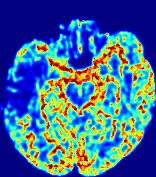

LesionRefer to captionRefer to captionRefer to captionRefer to captionRefer to captionRefer to caption𝐕rgbsubscript𝐕𝑟𝑔𝑏{\bf{V}}_{rgb}Refer to captionRefer to captionRefer to captionRefer to captionRefer to captionRefer to caption𝐕2subscriptnorm𝐕2{\|\bf{V}}\|_{2}Refer to captionRefer to captionRefer to captionRefer to captionRefer to captionRefer to captionRefer to caption3.53.53.52.82.82.82.12.12.11.41.41.40.70.70.70.00.00.0(mm/s)𝑚𝑚𝑠(mm/s)D𝐷DRefer to captionRefer to captionRefer to captionRefer to captionRefer to captionRefer to captionRefer to caption0.0200.0200.0200.0160.0160.0160.0120.0120.0120.0080.0080.0080.0040.0040.0040.0000.0000.000(mm2/s)𝑚superscript𝑚2𝑠(mm^{2}/s)Slice #1Slice #2Slice #3Slice #4Slice #5Slice #6

Figure 4: PIANO feature maps for another patient in the ISLES 2017 training set, where the lesion is located in the right hemisphere. Top row: segmented stroke lesion region (white) on different slices. The corresponding slices for the PIANO feature maps are shown in the following rows.

For a better insight into an estimated velocity field 𝐕𝐕{\bf{V}} and diffusion field 𝐃𝐃{\bf{D}}, we compute the following maps: (1) 𝐕rgbsubscript𝐕𝑟𝑔𝑏{\bf{V}}_{rgb}: Color-coded orientation map of 𝐕=(Vx,Vy,Vz)T𝐕superscriptsuperscript𝑉𝑥superscript𝑉𝑦superscript𝑉𝑧𝑇{\bf{V}}=(V^{x},V^{y},V^{z})^{T}, obtained by normalizing 𝐕𝐕{\bf{V}} to unit length and mapping its 3 components to red, green, blue respectively; (2) 𝐕2subscriptnorm𝐕2\|{\bf{V}}\|_{2}: 222 norm of 𝐕𝐕{\bf{V}}; (3) D𝐷D: scalar field in Eq. 5.

Fig. 3 and Fig. 4 show the PIANO feature maps estimated from two ISLES 2017 patients: all are highly consistent with the lesion in both cases. Details of the blood flow trajectories are revealed in 𝐕rgbsubscript𝐕𝑟𝑔𝑏{\bf{V}}_{rgb} by the ridged patterns and the sharp changes of colors in the unaffected (right) hemisphere, while the flat patterns appearing within the lesion provide little directional information about the velocity and indicate low velocity magnitudes. Velocity magnitudes are more directly visualized via 𝐕2subscriptnorm𝐕2\|{\bf{V}}\|_{2}, from which one can easily locate the lesion where 𝐕2subscriptnorm𝐕2\|{\bf{V}}\|_{2} is low. D𝐷D also indicates lower diffusion values in the lesion, though with less contrast potentially due to the fact that it captures the accumulated effect of CA diffusion at the voxel-level.